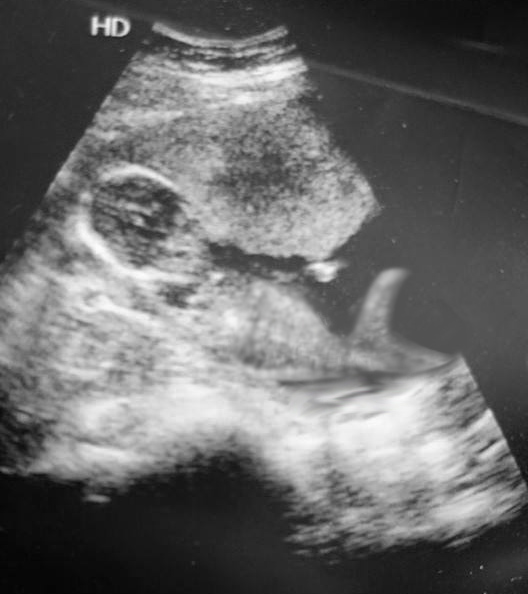

Attachment 28696

SaoirseMae, 15 weeks